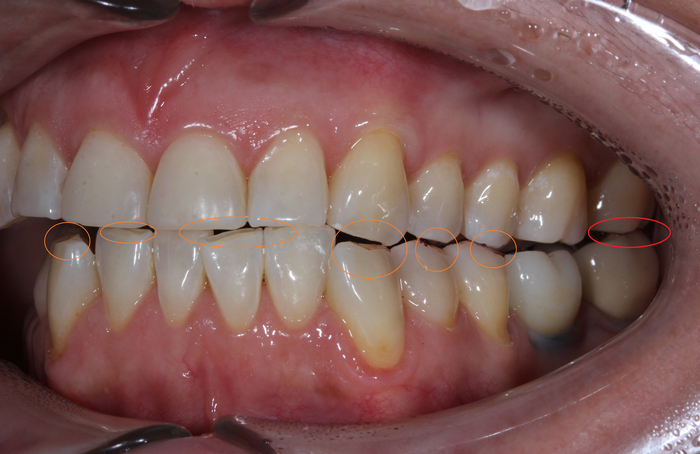

Обратите внимание, как сильно стерлась верхняя «двойка» и нижний клык:

Ниже ситуация от июня 2023:

Есть такое понятие, как клыковое ведение (или клыковая дезокклюзия) – это разобщение задних зубов во время боковых движений нижней челюсти. Иными словами, (прочтите медленно) при смещении нижней челюсти в сторону, двигаясь клыком нижней челюсти по клыку верхней челюсти на момент контакта бугров, у боковых зубов не должно быть контакта. В данном случае он есть именно на 7ках:

Оранжевым цветом отмечена стираемость зубов, а красным место контакта.

Зубы стерлись, высота прикуса занизилась. В связи с чем появился преждевременный контакт керамической коронки на нижнем 7м зубе (керамика не стирается) и верхним 7м зубом.

(Вы можете отметить, что на 6ке тоже керамическая коронка. Не стоит забывать, что ее переделывали. Следовательно, она была подогнана под истертые зубы).